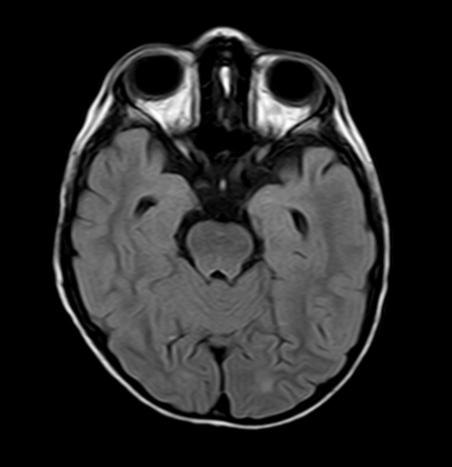

• RM craneal y medular: discreto aumento de señal en secuencia FLAIR y T2 en ambos hipocampos, algo más evidente en el izquierdo.